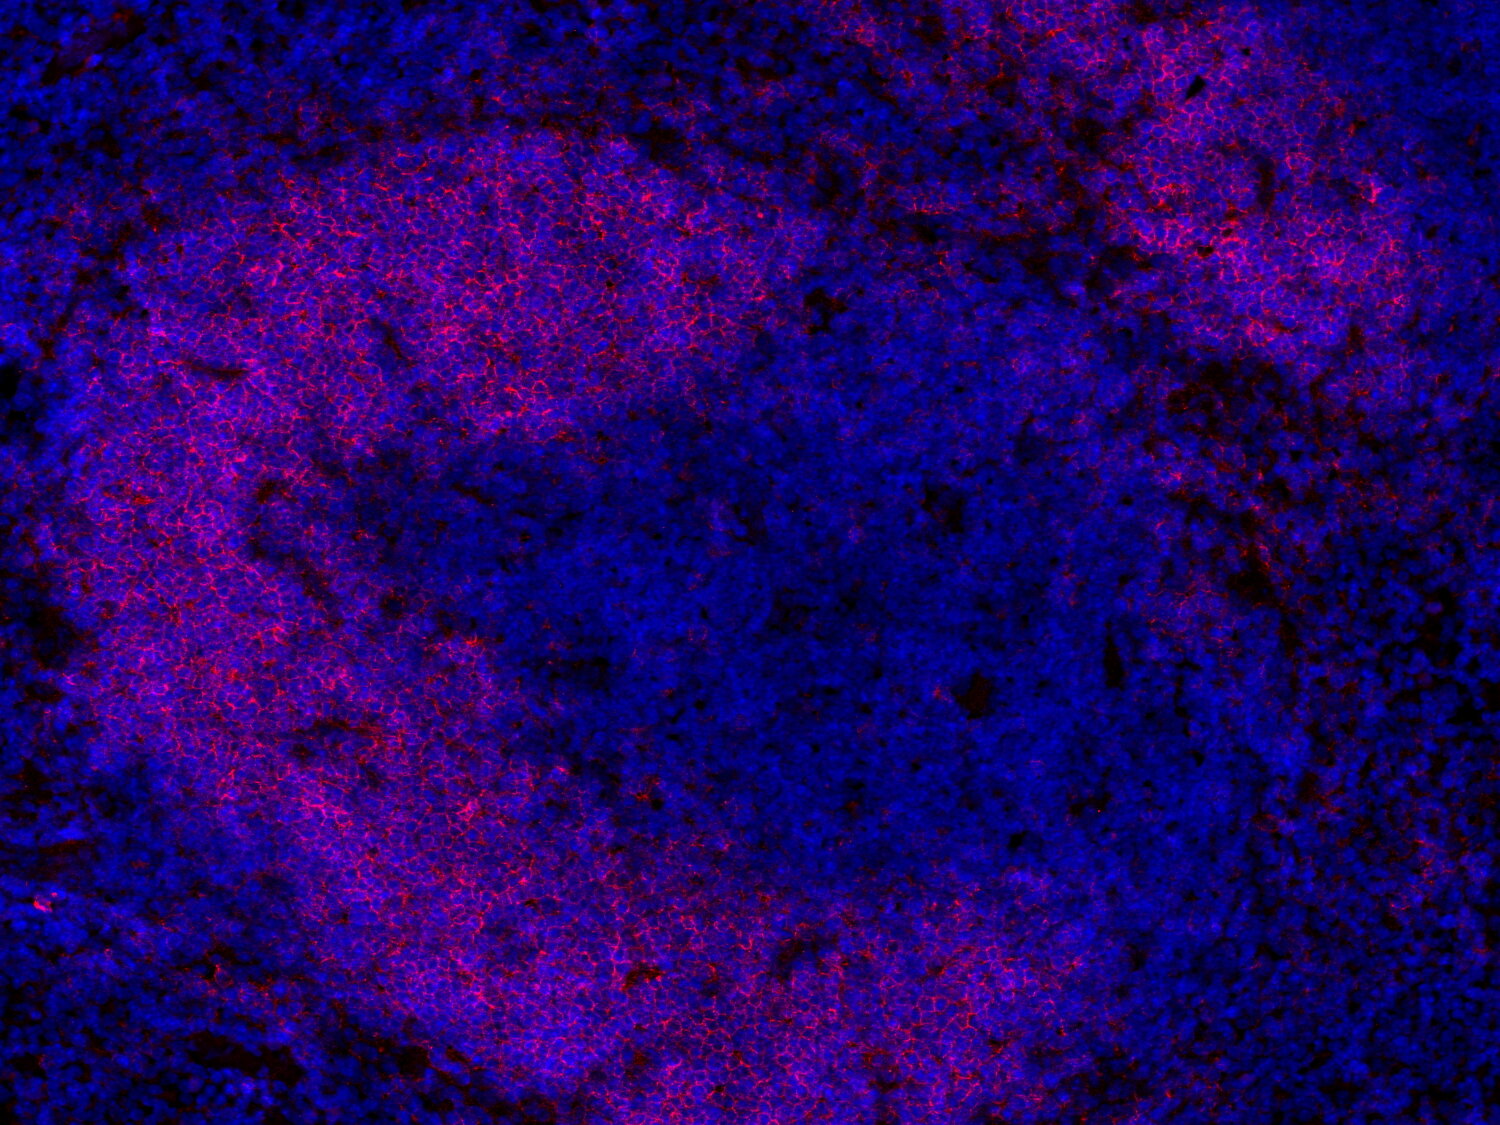

Fluorescent double staining for CD19 (red) and CD3e (green) visualizes B-cell and T-cell populations in the mouse spleen